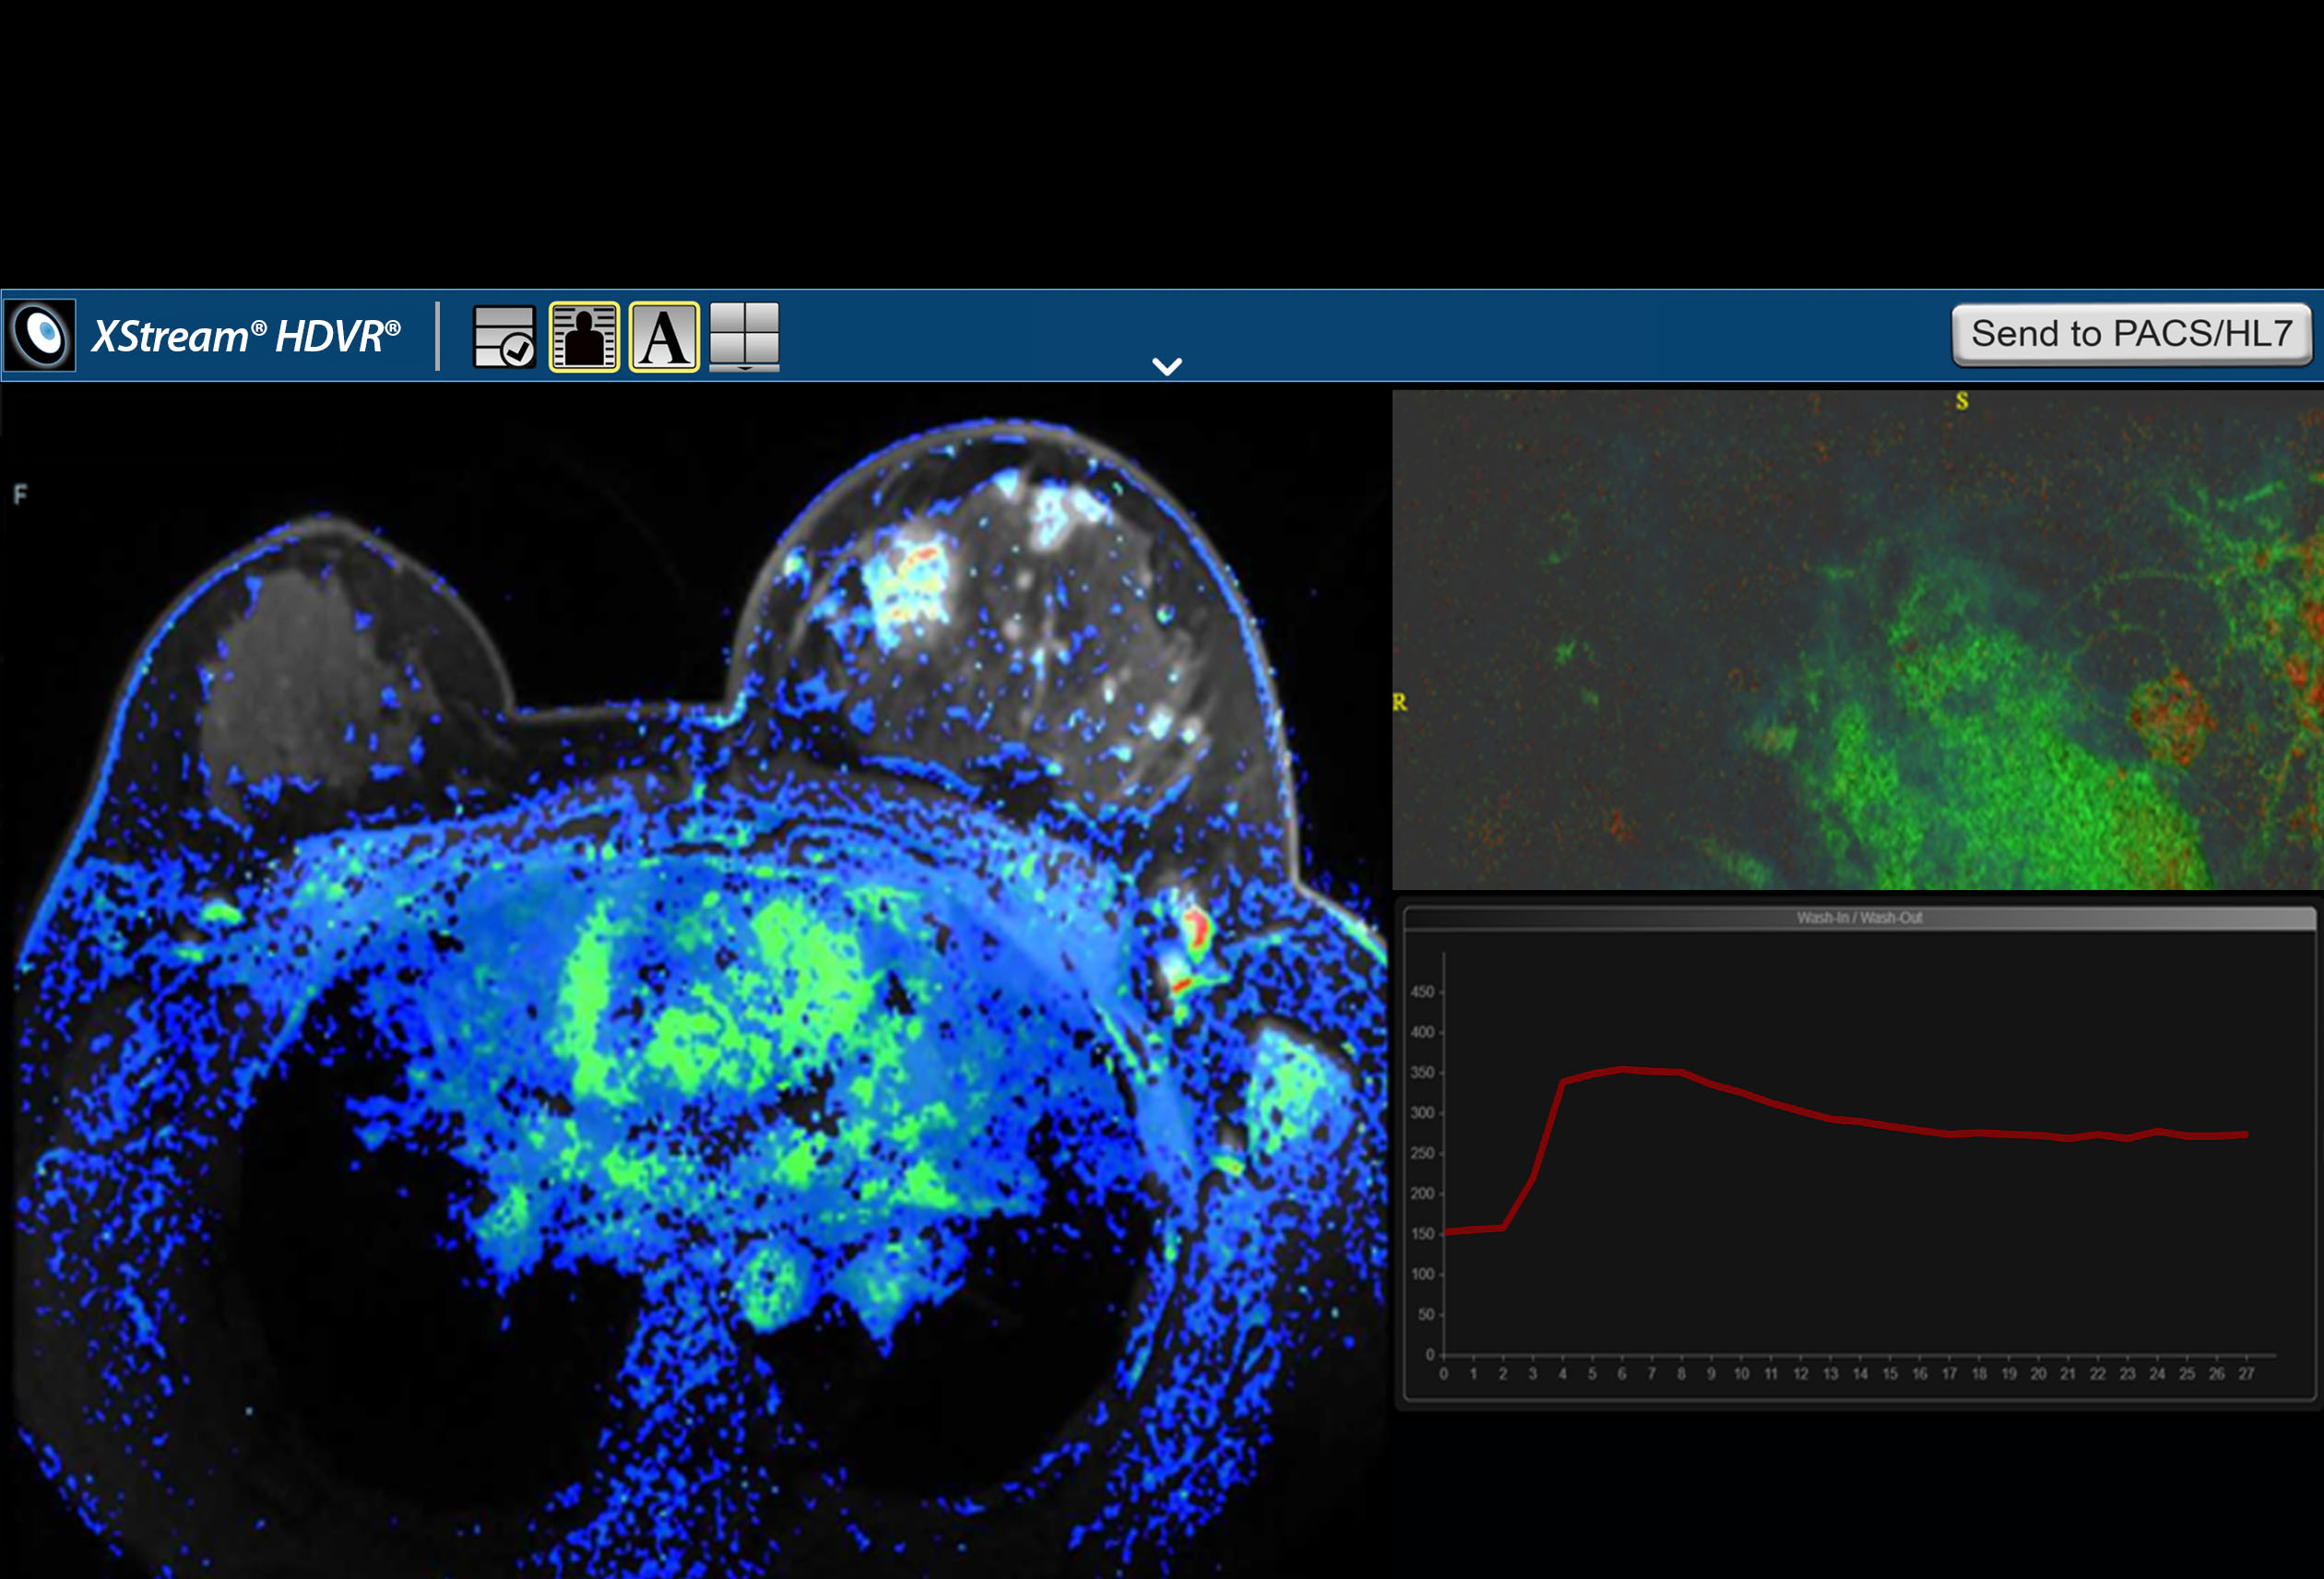

F.A.S.T. Multiparametric MRI Workflow

F.A.S.T. Multiparametric MRI Workflow